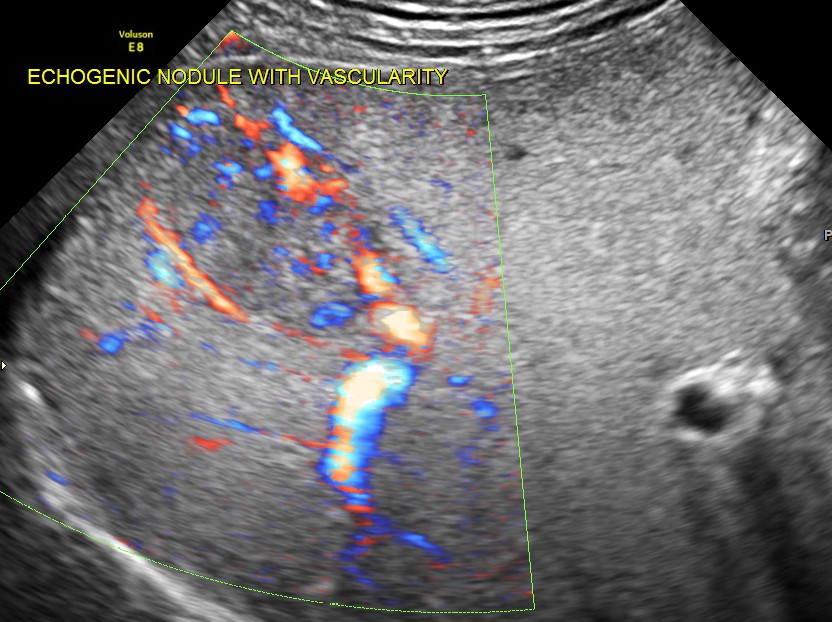

An echogenic nodule with vascularity is seen.

3 d reconstruction shows the solid nature and vascularity around and within the nodule.

The appearance of this nodule was suggestive of a metastatic nodule with the increased vascularity around and within.